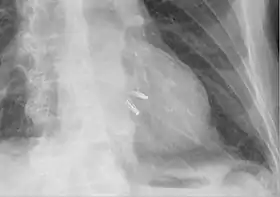

Chest radiograph showing two MitraClips projecting over the heart.